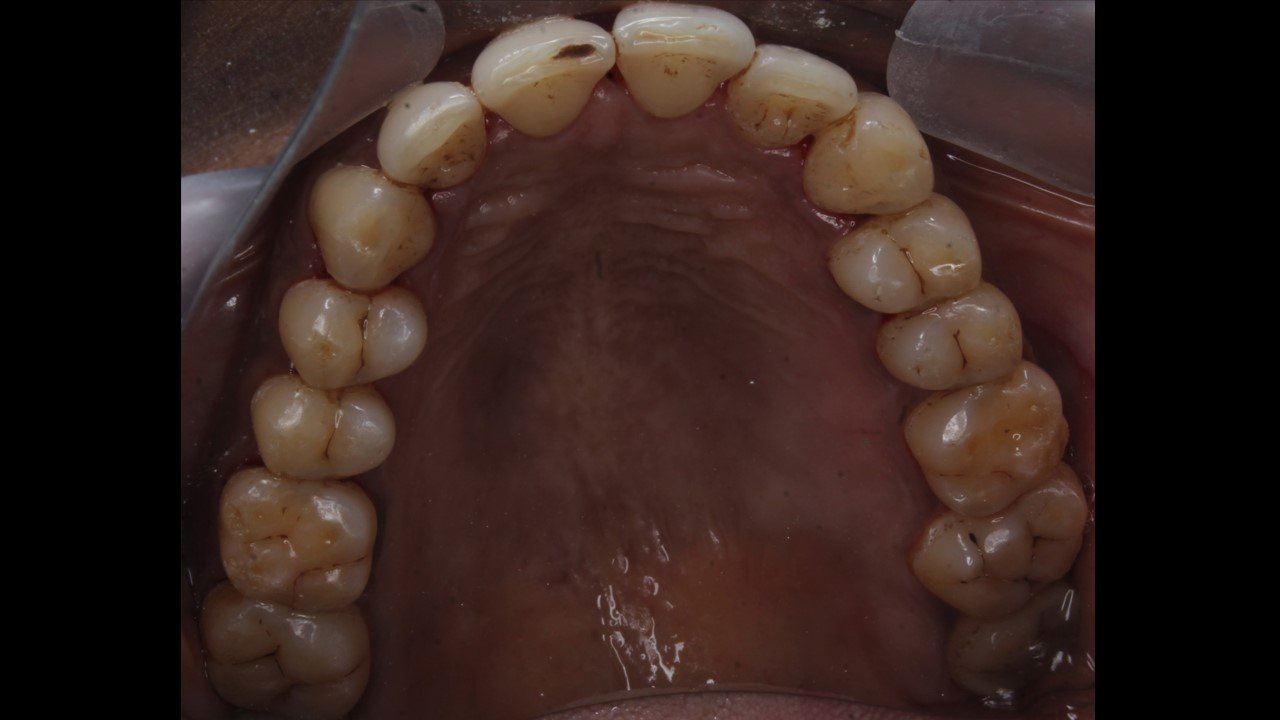

Case 1